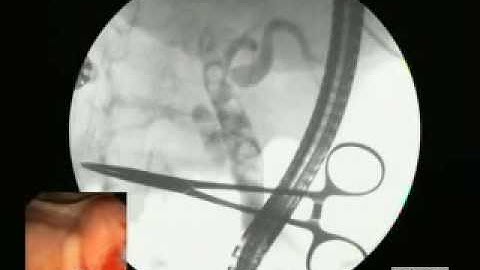

ERCP, nội soi mật tụy ngược dòng dùng needle - knife.